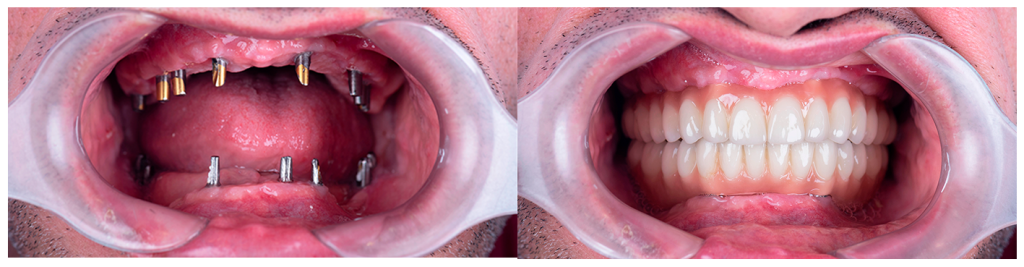

Casos de éxito